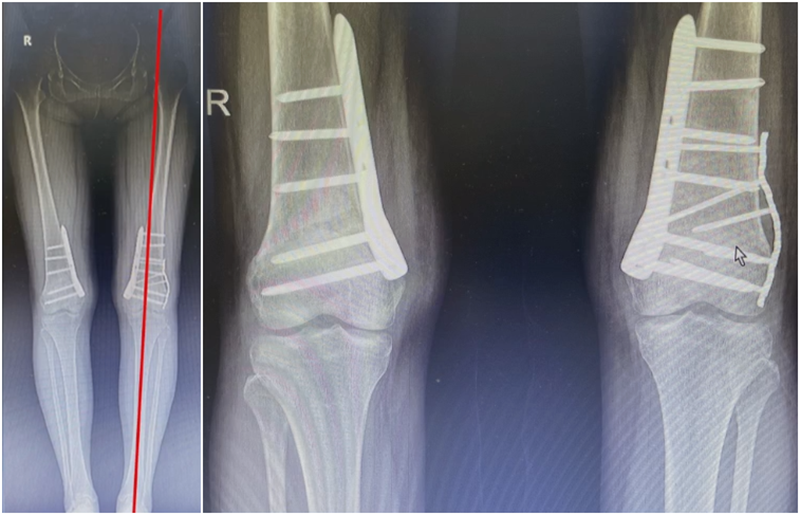

病例,X患者,女,双侧外翻膝,行双侧DFO。

术后6周摔伤,一侧出现膝内翻。

影像学检查显示左侧出现合页断裂。

进行翻修,术前力线显示内翻。

术中发现螺钉松动,截骨端出现坎插迹象。

近端螺钉松开,调整力线,重新固定后,在外侧加小钢板抗旋。

术后10周复查,力线较好。